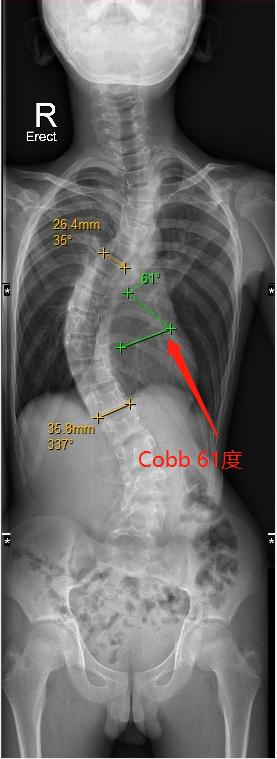

港大深圳医院脊柱外科主任、“三名工程”团队领军人张文智教授介绍,小磊曾使用过支具矫正脊柱,但效果并不理想。“小磊来到港大深圳医院治疗时,Cobb角已经达到了61度,远超过45度的手术干预指标,呈明显S形状,已经压迫到了心肺等主要器官。考虑到他的病情可能的恶化发展和手术预后,我们建议小磊立即进行手术干预。”

小磊手术前评估(左图),Cobb角度为61度,术后(右图)约为30度

在张文智教授团队及多学科共同合作下,小磊于5月3日进行了手术,手术时长约3小时,Cobb角由术前61度矫正为30度,手术进行得非常成功,“后续小磊只需要每2-3个月定期复诊一次即可。预计在植入的1-2个月后可撑开钛棒,并在未来三年内定期通过仪器进行体外拉伸,调整钛棒长度及脊柱角度,直到基本痊愈。”